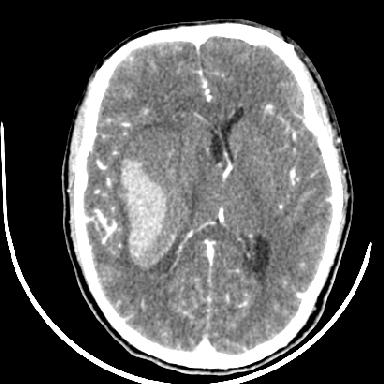

标题: CT6056:脑出血(血管畸形?) [打印本页]

标题: CT6056:脑出血(血管畸形?)

m 40突发头痛左侧偏瘫3小时

考虑高血压性脑出血,依据:

1是高血压性脑出血的好发部位,形态呈肾形,是高血压性脑出血的常见形状

2增强时占位效应加重了,考虑出血还没有停止

3病灶周围水肿不是太厉害,一般肿瘤出血水肿多非常明显

4病灶周围的‘软组织’影没有明显的强化

5至于脑血管畸形引起的出血,暂时没有看到明显的畸形血管影,也不太支持

支持右侧基底节脑出血

右侧基底节区脑出血.

支持右侧基底节区(主要为外囊区)原发性脑出血。

另附部分资料:“血液溢出血管外形成血肿,其内含有大量血红蛋白、血浆白蛋白,球蛋白,因这些蛋白对x线的吸收系数高于脑质,故ct呈现高密度阴影,ct值达40~90h,最初高密度灶呈非均匀一致性,中心密度更高,新鲜出血灶边缘不清。基底节区血肿多为“肾”型,内侧凹陷,外侧膨隆,因外侧裂阻力较小,故向外凸,其它部位血肿多呈尖圆形或不规则形”

术中抽出40ml陈旧血液,血肿底部似见一条索血管影